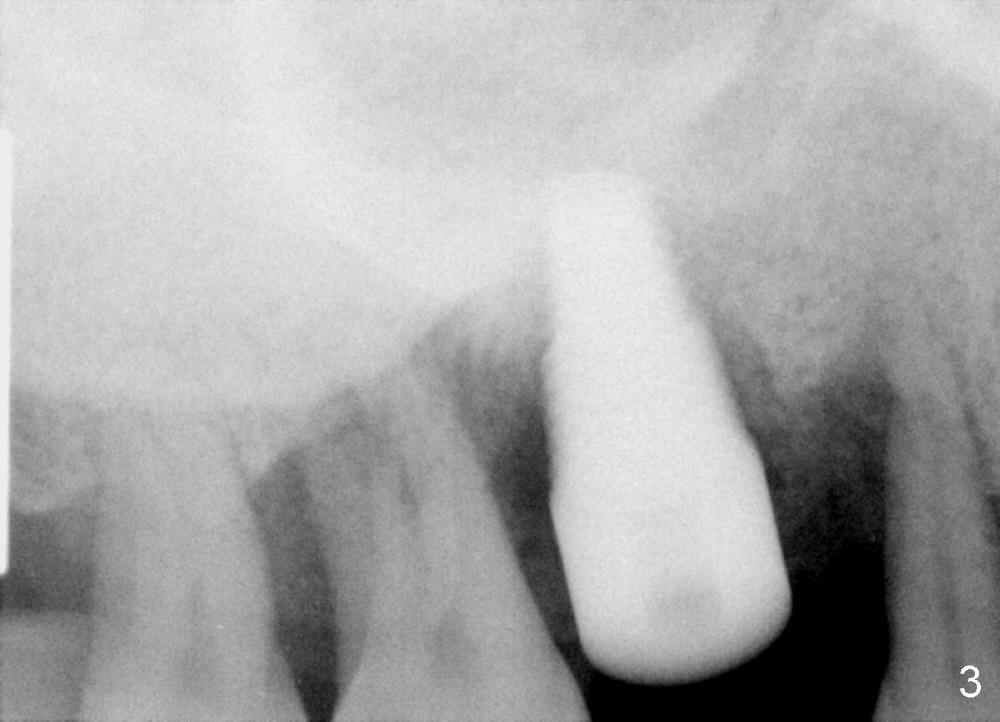

It is my pleasure to have met you in AAID meeting and have discussed one of my cases.  It tells me that good treatment planning is critical.  Can you help me deal with a case of potential bad treatment plan?  A 40-year-old man has severe periodontal disease (Fig.1).  It must be the best case for hybrid denture.  Unfortunately, three months ago, the teeth #8,9 were extracted due to mobility and replaced with immediately provisionals (Fig.2: taken 1.5 months postop).  The uniposts were permanently cemented.  Temporary crowns look long.

Then how can we remove the permanently cemented abutments from the implants at the sites of #8 and 9 (Fig.2)?  Thanks.

Dr Wei,  The cervical position of the centrals looks perfect in relationship to the laterals.  The long crowns are a result of the perio bone loss just as the laterals are longer for the same reason.  The posts cannot be removed now that they are cemented.  The decision to use a hybrid denture must be made at the time of initial treatment planning.  Dr B 11/05/2013